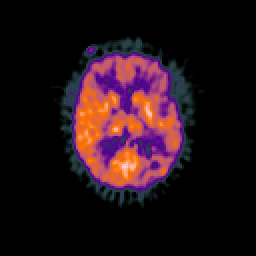

Glioma overlay -- Slice #62

[Home][Help][Clinical] Slice 62